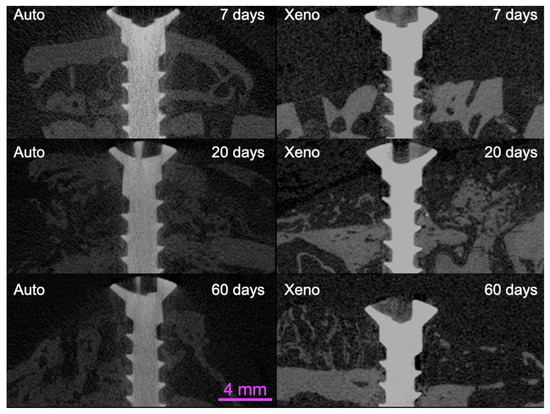

3.2. Micro-CT Evaluation

| TV | BV | ||

|---|---|---|---|

| 7 days | Auto | 258.3 ± 15.8 * | 52.8 ± 7.7 * |

| Xeno | 166.9 ± 26.0 * | 4.2 ± 0.4 | |

| 20 days | Auto | 159.5 ± 77.1 | 27.2 ± 11.1 |

| Xeno | 166.4 ± 50.3 | 18.8 ± 9.5 | |

| 60 days | Auto | 107.2 ± 17.5 * | 33.1 ± 2.8 *** |

| Xeno | 96.0. ± 19.1 * | 7.6 ± 3.7 *** |